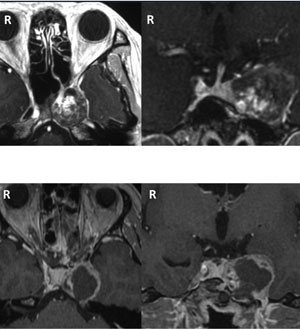

上段:海綿静脈洞部三叉神経鞘腫術前

下段:内視鏡下経鼻頭蓋底手術後